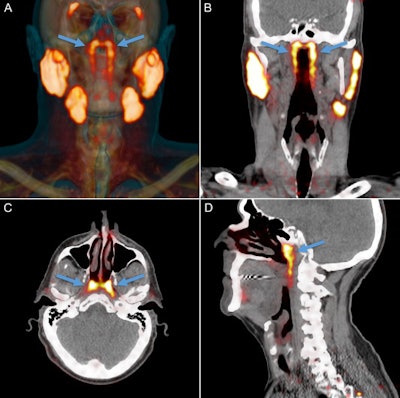

PSMA-PET/CT can visualize salivary glands with high sensitivity and specificity, Valstar and colleagues wrote. This allowed the researchers to observe an unknown bilateral structure posterior in the nasopharynx, with radiopharmaceutical uptake much like that of the known major parotid, submandibular, and sublingual salivary glands.

Valstar and colleagues evaluated PSMA-positive tissues in the nasopharynx on PSMA-PET/CT scans from a retrospective study of 100 consecutively scanned patients with prostate or urethral gland cancer. In addition, morphological and histological characteristics were assessed in two human cadavers.

All 100 patients with prostate or urethral gland cancer demonstrated a divided bilateral PSMA-positive area with an average length of 4 cm. Examining the glands and 3D reconstruction confirmed the presence of PSMA-expressing, predominantly mucous glands with multiple draining ducts. They were found predominantly near the torus tubarius, according to the authors.